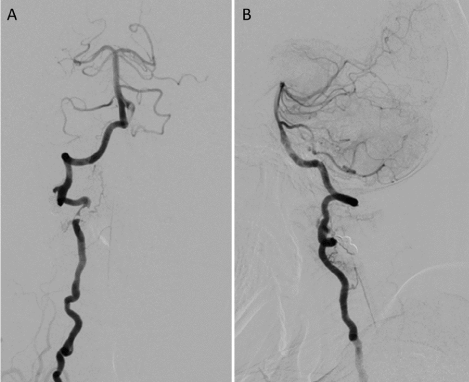

All previous imaging studies were reviewed and found that multiple recent infarctions had occurred on several areas in different time during period of 3 years. These infarcts involved bilateral thalami, midbrain, pons, left cerebellum, and bilateral medial temporo-occipital lobes. In our institute, MRI of the brain obtained 3 years after initial onset revealed multiple old infarctions in bilateral thalami, bilateral cerebellum, brainstem, and bilateral temporo-occipital lobes. There were encephalomalacic changes of bilateral occipital lobes. Susceptibility weighted imaging (SWI) and T2*-weighted gradient-recalled echo (GRE) image demonstrated evidence of old hemorrhagic transformations (Figure 2). Maximum intensity projection from 3D time-of-flight MRA of the cervical spine also showed an abnormal tubular-like lesion projected from posterolateral aspect of the right V3 segment between the level of C1 and C2. Also, there were irregularity and tortuosity of bilateral V1 and V2 segments (Figure 3A). The digital subtraction angiography (DSA) was further investigated and demonstrated the right VVAVF located at the level of C1-2 and drained directly into deep cervical veins (Figure 3B and 3C).

Figure 2. Follow-up magnetic resonance imaging (MRI) of the brain obtained 3 years after initial onset. Sequential images of axial fluid-attenuated inversion recovery (FLAIR) MRI at the upper (A) and lower (B) level of the brain reveal bilateral thalamic infarcts. Sequential images of axial T2-weighted MRI at the level of midbrain (C) and pons (D) also disclose multiple infarctions in brainstem and right cerebellum. There are encephalomalacic changes of bilateral occipital lobes. Axial susceptibility weighted imaging (SWI) (E) and coronal T2*-weighted gradient-recalled echo (GRE) image (F) show evidence of old hemorrhagic transformations